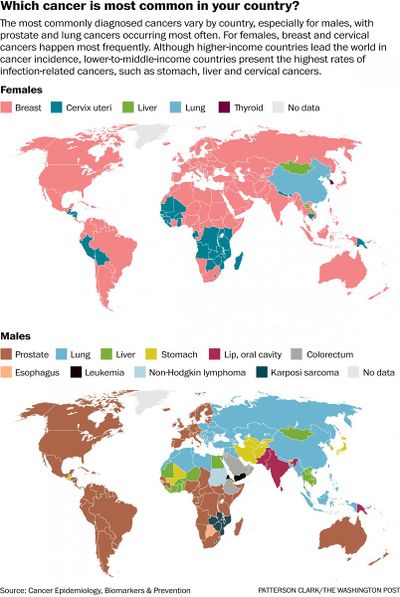

السرطانات الثلاثة عشر الشائعة

| نوع السرطان | الانتشار |

|---|---|

| سرطان القولون والمستقيم | 9.4 مليون |

| اللمفوما اللاهودجكينية | 4.3 مليون |

| سرطان المثانة | 3.4 مليون |

| سرطان الرئة | 3.3 مليون |

| الميلانوما | 3.1 مليون |

| اللوكيميا | 2.3 مليون |

| سرطان الثدي | 2.1 مليون |

| سرطان المبيض | 1.2 مليون |

| سرطان الپروستاتا | 1.1 مليون |

| سرطان الكبد | 618.700 |

| سرطان الرحم | 528.000 |

| سرطان الكلى | 208.500 |

| سرطان البنكرياس | 393.800 |

| المصدر: مجلس السرطان | |

ويستعرض المقال حقائق وأرقام عن السرطانات الأكثر شيوعاً في العالم بصفة عامة، والمنطقة العربية بصفة خاصة.